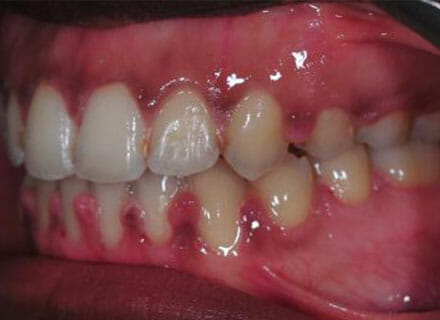

Open bite, protruding upper teeth

How a big open bite can be closed down while at the same time straightening all the teeth and closing gaps! Using clear fixed braces over around 18 months. Please note that the swollen gums in the after photos are what happens if a patient is not cleaning carefully enough or seeing the hygienist during treatment – after careful cleaning and hygiene treatment these gums returned to normal!